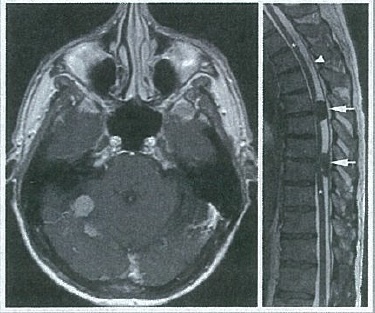

45 year old woman

Cerebellopontine angle tumor, most likely a Schwannoma aka Neurilemoma